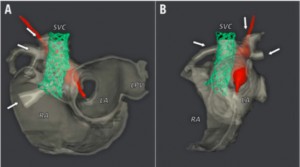

疾患としては図の通り上大静脈下端付近に欠損孔が存在し、後方に存在する左心房との交通を認めます。経過は二次孔欠損型とほぼ同様ですが、洞不全症候群や上室性頻脈の割合が高いなどの特徴があります。病態的な治療適応は二次孔欠損型と同様で右心負荷や血栓症既往などが挙げられます。一方、形態的にはカテーテル治療の適応は慎重な判断が必要です。右房の後方にある右肺静脈部や右肺静脈―左心房接合部付近が、欠損孔になることがほとんどであるため、ステント留置後の右肺静脈圧排、閉塞に注意が必要です。当施設ではMRIによる血行動態評価、経食道エコー、造影CTによる形態評価を行い、さらにCT画像を元に3Dプリンターで疾患モデルを作成し3次元的にステント留置が可能かを評価しています(図2, 図3)。